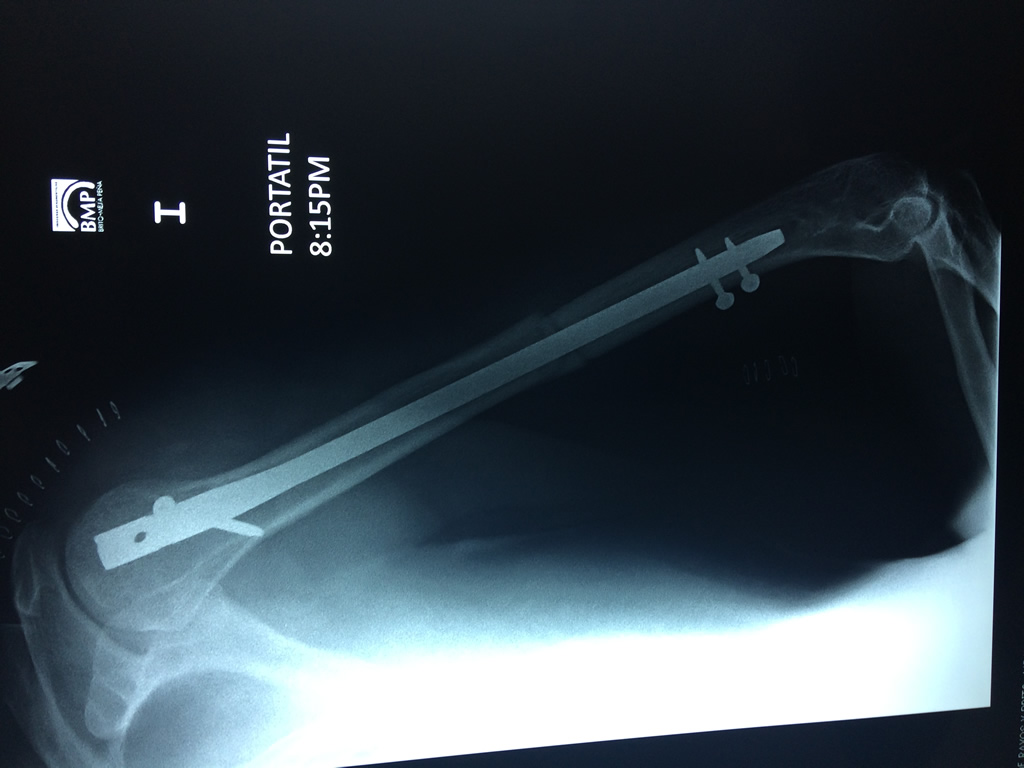

Cirugías de Calcaneo - Húmero

El Húmero (en latín, humerus) es el hueso más largo de las extremidades superiores en el ser humano. Forma parte del esqueleto apendicular superior y está ubicado en la región del brazo. ... El extremo proximal del húmero tiene la cabeza, cuellos quirúrgico y anatómico y tubérculos mayor y menor.